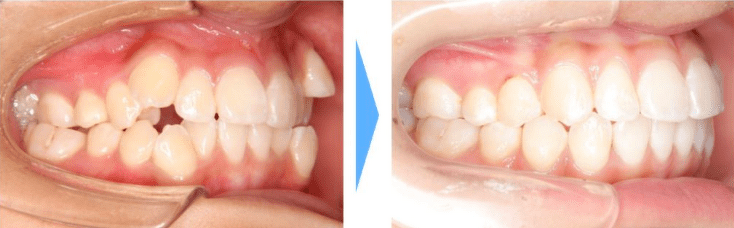

【叢生】

歯並びがガタガタしている、八重歯が歯並びから大きく外れているなど歯並びが大きく乱れます。その影響で唇がへこんだり膨らんだりすることで口角がくぼんだり下がったように見えます。

症例情報

【患者】 10代女性

【主訴】 八重歯

【治療期間】1年9ヶ月 通院回数17回

【治療内容】マウスピース型カスタムメイド矯正歯科装置(製品名インビザライン 完成物薬機法対象外)を使用して主訴である叢生の改善を行いました。

【費用】88万(税込)

【リスク】矯正歯科装置を付けた後しばらくは違和感、不快感、痛みなどが生じることがあります。

矯正中は矯正歯科装置が歯の表面についているため食物が溜まりやすく、また歯が磨きにくくなるため、虫歯や歯周病が生じるリスクがあります。

歯を動かすことにより歯根が吸収して短くなることや歯肉がやせて下がることがあります。